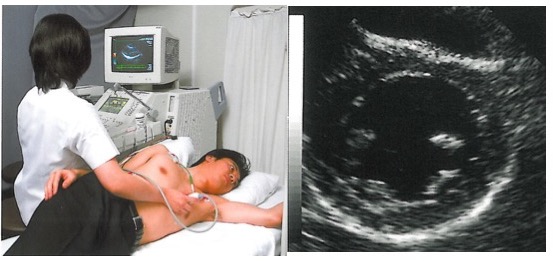

その際にお勧めしているのが、心エコー検査(図1)です。

超音波を用いて痛みなどを伴わずに心臓の機能を詳しくみる検査です。体に負担をかけることなく、心臓の機能がよくわかります。心臓の動きにかたよりがないかどうか、心臓にある弁(逆流防止のとびら)の機能はどうか、などをみることができます。これらによって、心臓の血管に詰まりがないかどうか、心臓の弁などの異常により心臓に負担が来ていないかどうかがわかるのです。